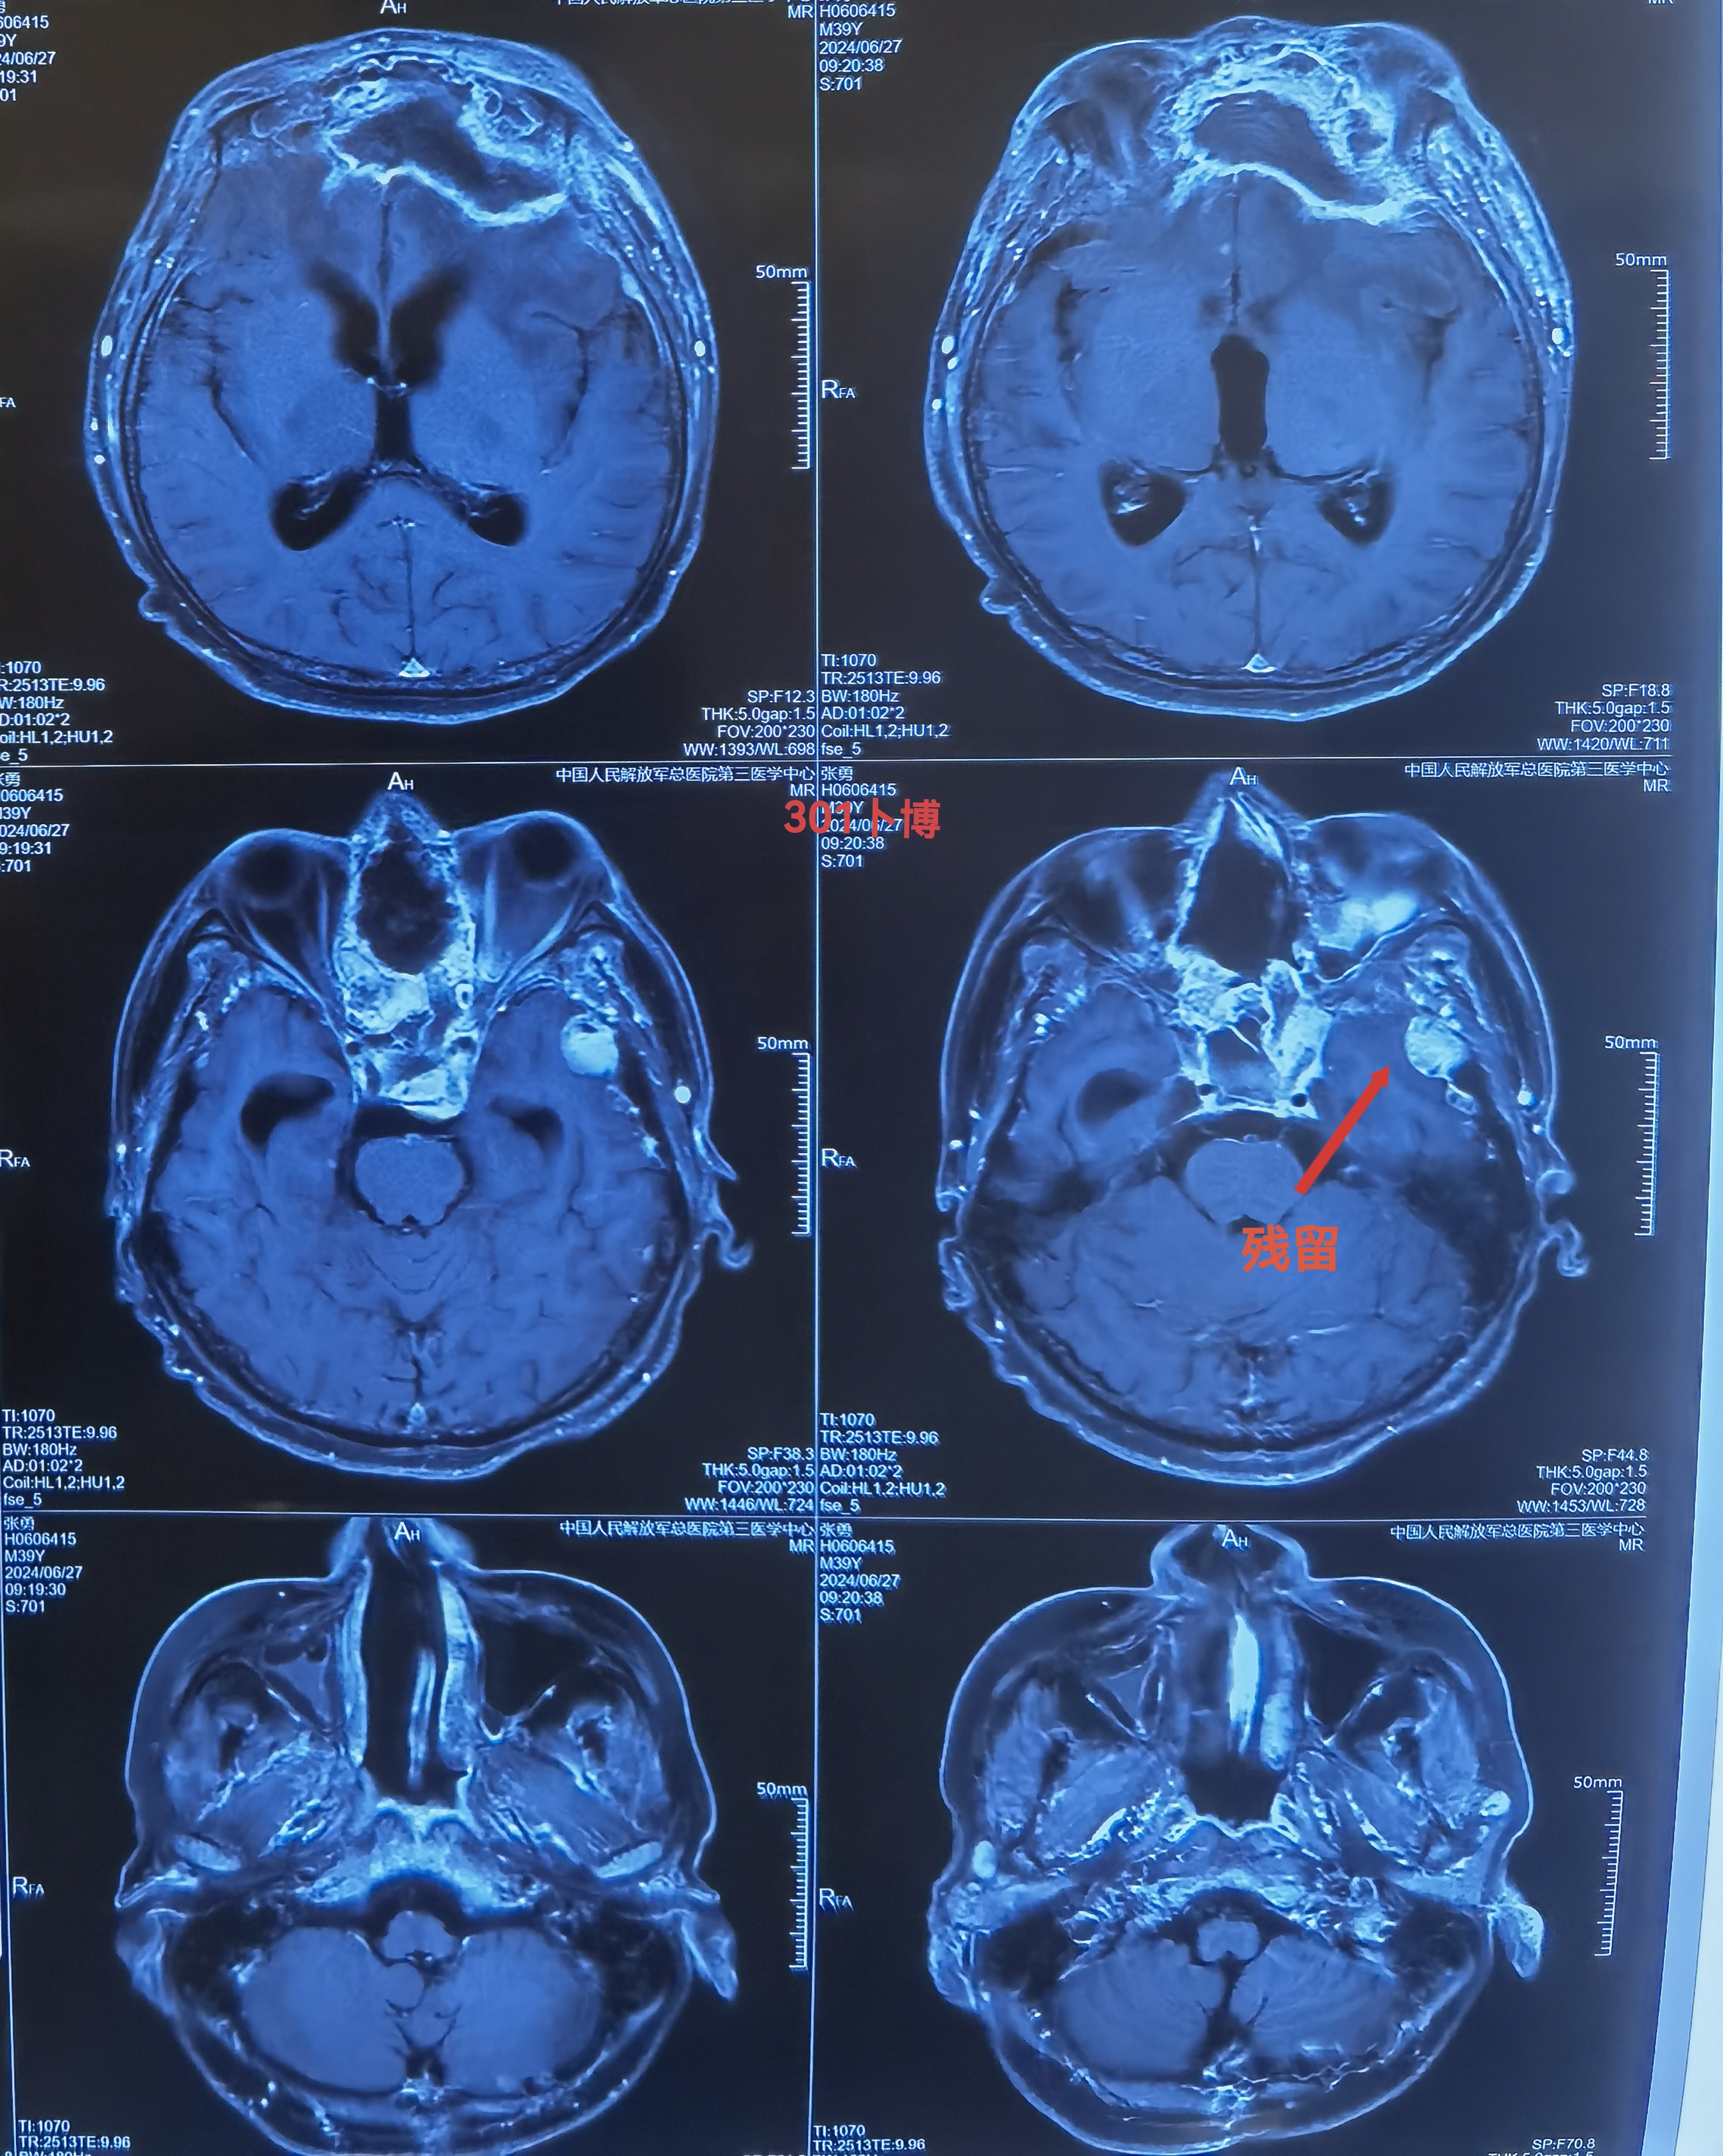

术后复查,提示切除理想。颅内的低密度改变为脂肪组织。

术后一个半月,肿瘤切除理想。

术后一个半月,肿瘤切除理想。既往未做放疗,建议做全脑加局部伽马刀。